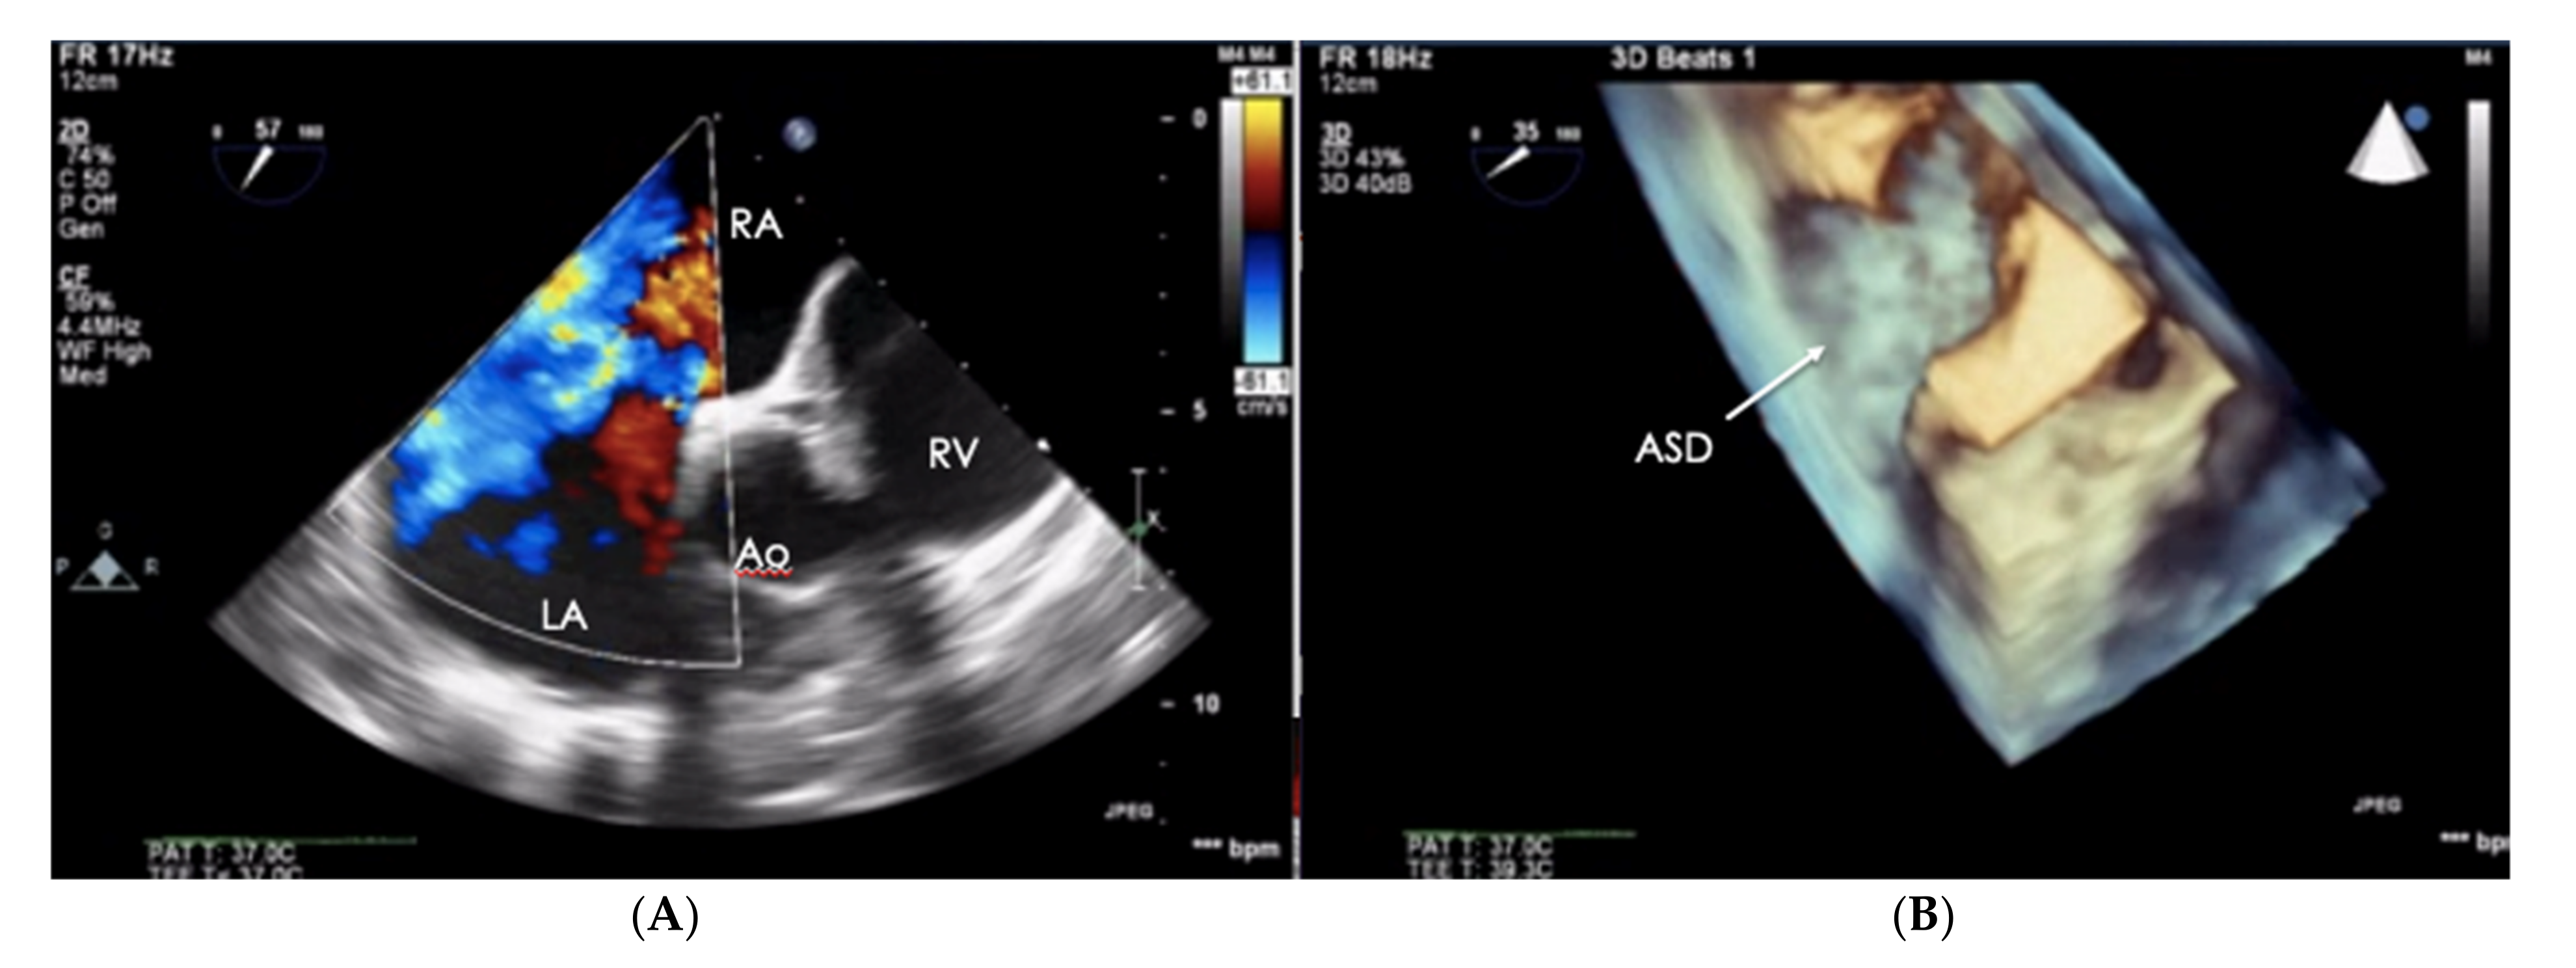

When assessing the right heart′s size, the dimensions of the right atrium (RA) should not be overlooked (Figure 6). The linear dimension of RA should be marked in the 4CH view, perpendicular to the long axis of the heart (Figure 7) [23]. However, more valuable in terms of clinical significance is the RA volume, also measured in the 4CH view [23]—an RA area greater than 18 cm2 indicates enlargement and is one of the most common echo abnormalities found in PAH patients [24].

Figure 6.

Patient with PAH-CHD–atrial septal defect. (A) 2D-TTE visualization, short-axis view (SAX). (B) The same defect visualized in the transthoracic echo (TTE), 3D visualization. PAH-CHD: pulmonary arterial hypertension-congenital heart disease; 2D-TTE: two-dimensional transthoracic echocardiography.